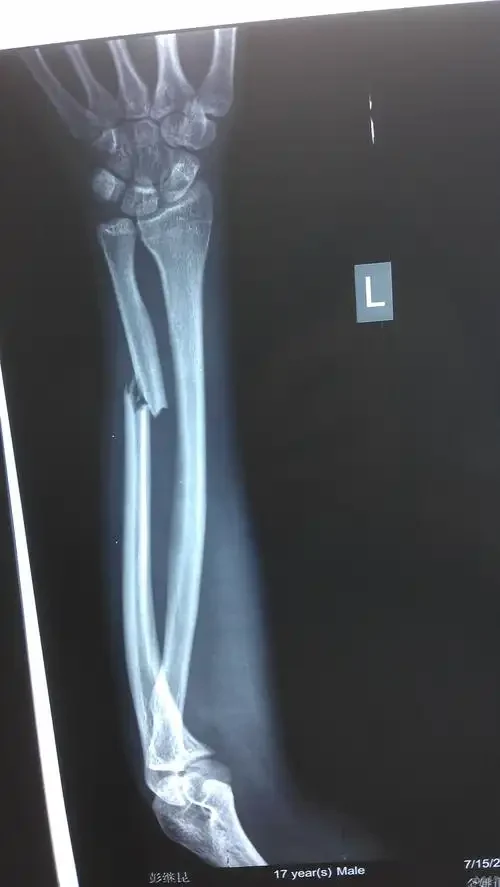

开放性胫骨和腓骨骨折是一种严重的骨骼损伤,通常是由意外创伤造成的。这种类型的骨折不仅涉及到骨骼的折断,还包括皮肤和其他软组织的破裂,可能伴随显著的失血和感染风险。因此,这种骨折类型需要紧急就医和外科手术干预。

患者接受的“胫骨骨折切开复位钢板内固定术”是处理这种骨折的一种标准方法。在手术中,医生会首先进行病灶区域的清创,去除感染源,随后对骨折部位进行复位。复位完成后,通过钢板和螺钉将骨折的骨骼片段固定在正确的位置,以确保骨骼能够正常愈合。整个过程中非常重要的一步便是对伤口的彻底清创,这是避免感染的关键。